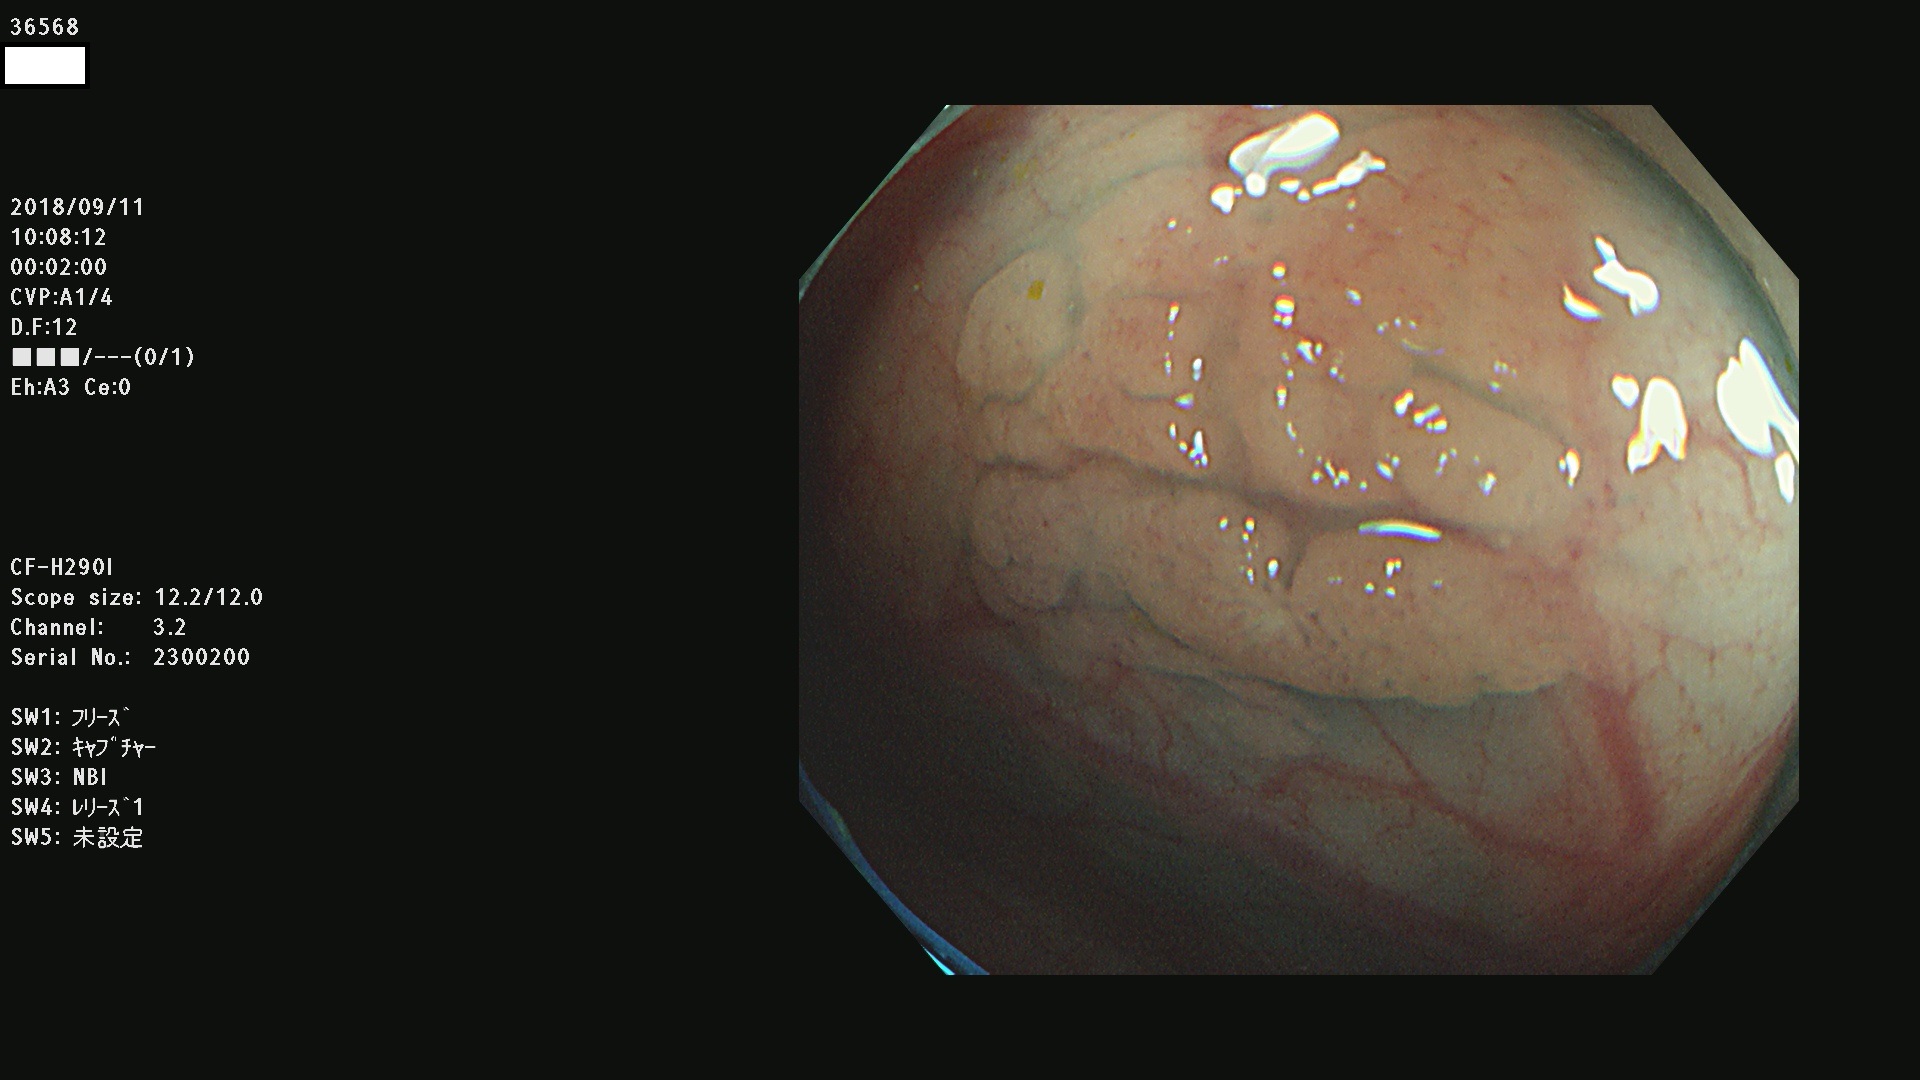

36500 36503 36504 36505 36507(SSAPのみ) 36508 36509 36510 36511 36514 36515 36517 36518 36520 36522(SSAPのみ) 36523 36524 36526 36528 36530 36531 36532 36533 36534 36535 36536 36538 36541 36542 36543 36544 36545 36546 36548 36550 36551 36554 36555 36556 36558 36559 36560 36561 36564 36565 36567 36568 36570 36572 36573 36574 36575 36576 36577 36578 36579 36580 36582 36584 36586 36591 36592 36593 36594 36595 36596 36597 36598

発見困難で危険性の高い平坦型病変(上記100名より抽出)